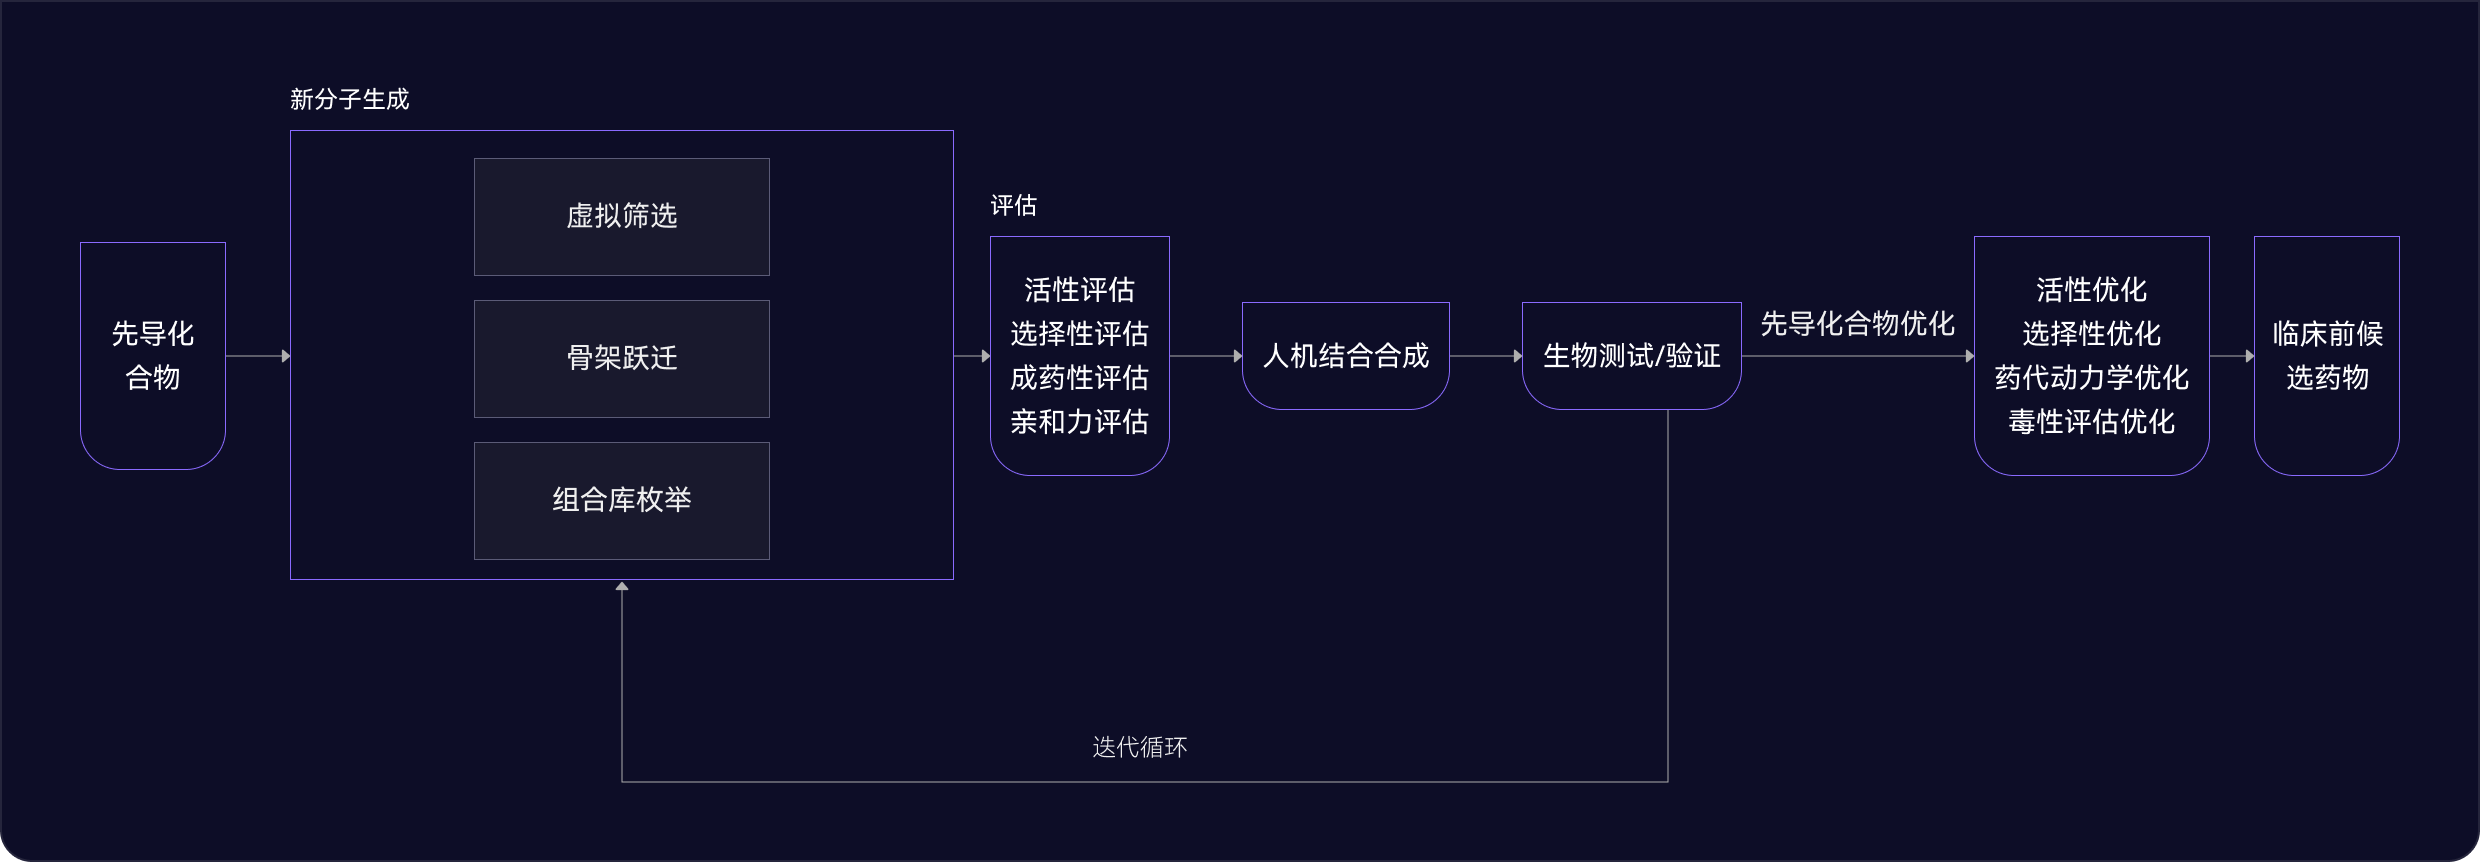

05 先導化合物階段

尋找最佳先導化合物

并優化成藥性質

先導化合物評估與優化

通過優化活性、選擇性和類藥性,將苗頭化合物轉化為先導化合物

- 利用生成式AI(XMolGen)進行分子和庫設計,增加骨架新穎性和化合物多樣性

- 通過先進的物理計算(XFEP)進行虛擬篩選,優化活性和類藥性

- 通過專有自動化平臺,實現快速且可靠的中間體和庫合成

自動化助力先導化合物優化

在進入臨床前試驗前,優化先導化合物提高療效和安全性,改善藥代動力學特性。

- 借助自動化濕實驗室化學能力,快速而穩健進行SAR分析,指導化合物設計

- 內部動物實驗室支持體內研究,包括藥代動力學/藥效學(PK/PD)、療效、安全性、劑量和代謝,推進臨床前開發

- 先進的力場技術,準確計算自由能微擾,預測結合親和力